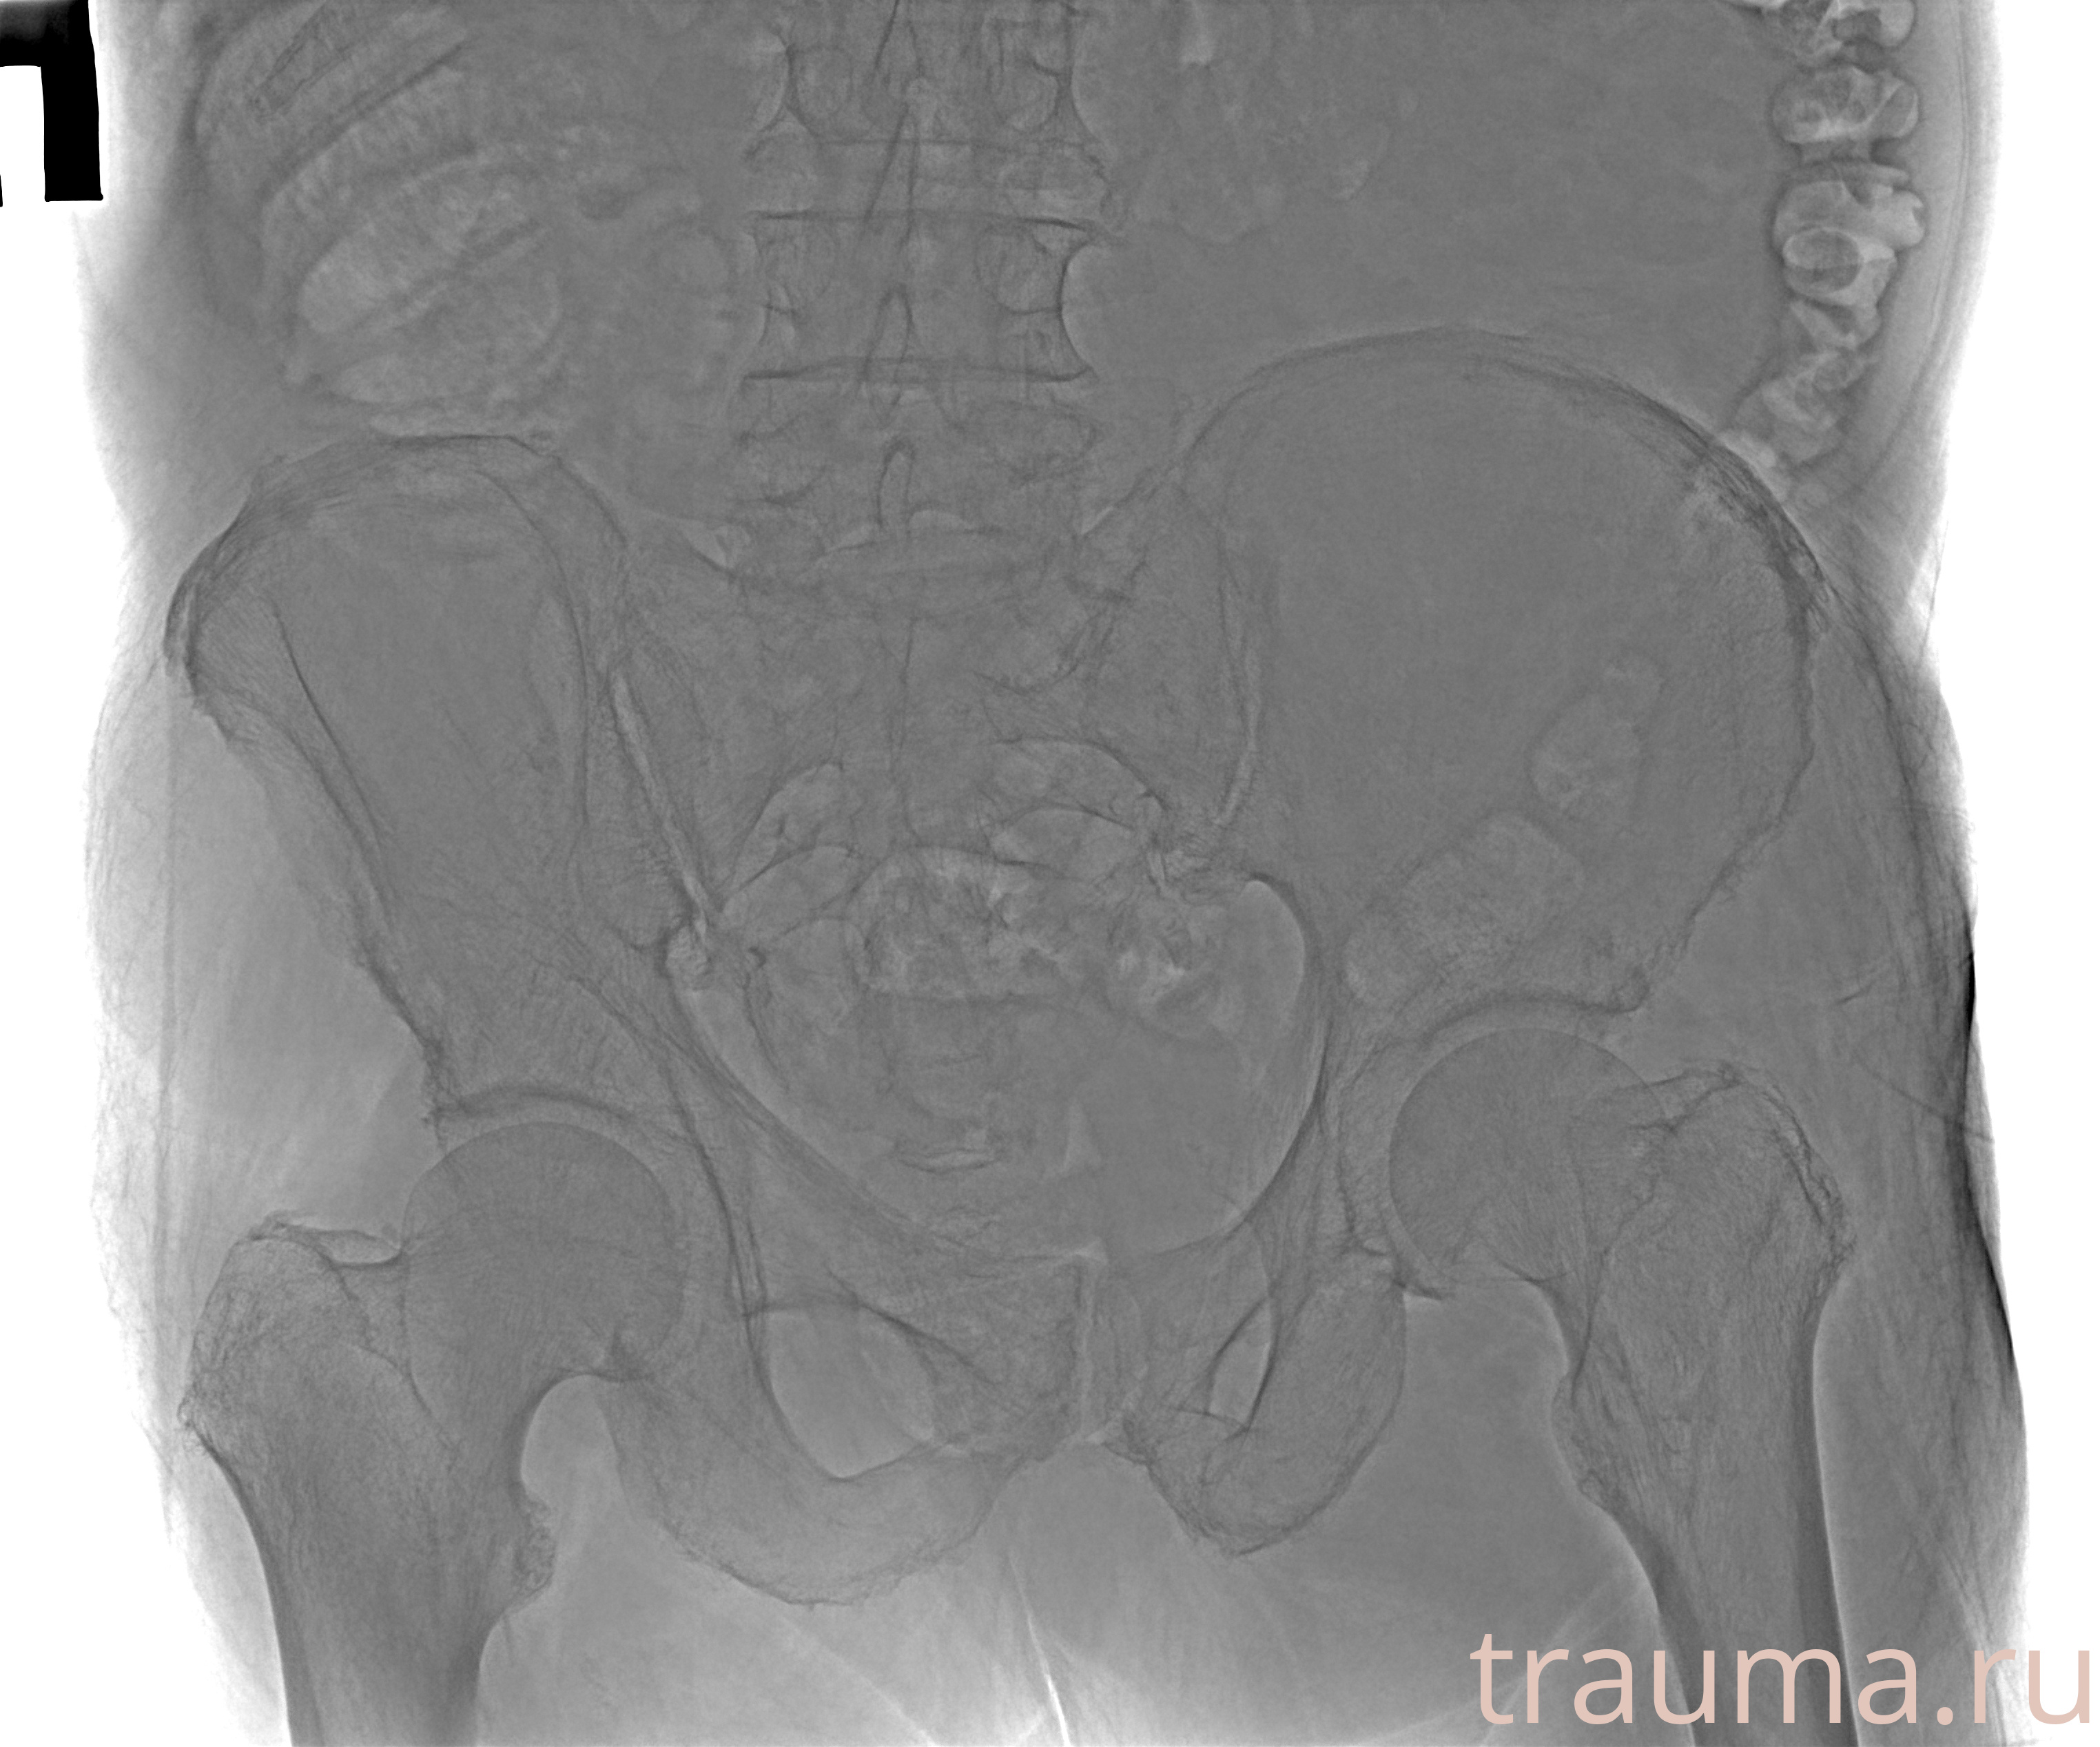

Рентгенограммы

Рентген на дому: по вашему адресу приезжает врач-рентгенолог, травматолог-ортопед с мобильным рентгеновским аппаратом, проводит диагностику травмы или заболевания, делает необходимые рентгенограммы, дает рекомендации по дальнейшему лечению. Получить качественные снимки в домашних условиях возможно благодаря уникальной методике, разработанной МосРентген Центром для института  Склифосовского